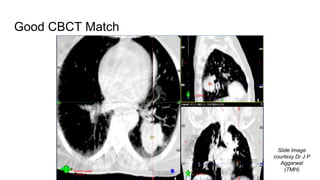

Good CBCT Match

Slide Image

courtesy Dr J P

Aggarwal

(TMH)

Good CBCT Match SlideImage courtesy Dr J P Aggarwal (TMH)

• #20 Bone matching results in signifcant residual errors at the level of the tumor. If using CBCT it is better to match with the soft tissues.